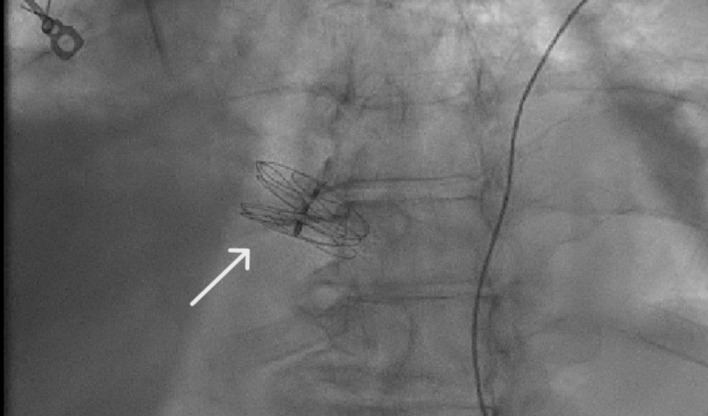

呼吸困难是一种令人痛苦的症状,表现为直立时呼吸困难,躺下时症状明显改善。与仰卧位时呼吸困难加重的正位性呼吸困难形成鲜明对比的是,POS 在从躺下到站立的过程中会出现血氧饱和度降低的独特症状。这种综合征症状微妙,给诊断带来了挑战,需要临床高度怀疑才能准确识别。在此,我们介绍了一例病史复杂的 79 岁女性患者,其主要病史包括深静脉血栓(DVT)和随后的肺栓塞(PE),需要长期服用华法林进行抗凝治疗;乳腺癌肿块切除术和化疗后病史;高血压和慢性肾脏疾病(CKD)。患者因持续低氧血症和提示 POS 的临床特征从一家生活机构入院。尽管进行了全面的体格检查和常规实验室检查,但未发现明显异常。然而,超声心动图检查发现了严重的卵圆孔未闭(PFO)和右向左分流,证实了 POS 的诊断。随后,医生使用 GORE CARDIOFORM 室间隔封堵器对 PFO 进行了经皮封堵,透视检查证实封堵器成功置入了房间隔内。值得注意的是,患者术后的氧合情况明显改善,并在两天内出院。POS 虽然罕见,但由于其可能导致相当高的发病率和死亡率,因此具有重要的临床意义。POS 的病理生理学基础在于肺血流和全身血流之间的不协调,最终导致患者在采取直立姿势时出现动脉饱和度降低。及时识别和干预对于减轻症状负担和避免相关并发症的恶化至关重要。早期诊断有助于实施有针对性的治疗策略,从而缓解呼吸困难,防止该综合征引发不良后遗症。因此,提高医护人员对 POS 细微表现的认识对于加快适当的管理和优化患者预后至关重要。

Platypnea-orthodeoxia syndrome (POS) is an uncommon yet clinically significant medical phenomenon characterized by dyspnea, a distressing symptom manifesting as breathlessness upon assuming an upright position, which notably improves upon reclining. In stark contrast to orthopnea, where dyspnea worsens in a supine position, POS uniquely presents with decreased blood oxygen saturation upon transitioning from lying down to standing up. This syndrome poses diagnostic challenges due to its subtle symptomatology and requires a high index of clinical suspicion for accurate identification. Herein, we present a case of a 79-year-old female with a complex medical history, notably encompassing deep vein thrombosis (DVT) and subsequent pulmonary embolism (PE) necessitating long-term anticoagulation with warfarin, a history of breast cancer status post lumpectomy and chemotherapy, hypertension, and chronic kidney disease (CKD). The patient was admitted from a living facility with persistent hypoxemia and clinical features suggestive of POS. Despite comprehensive physical examination and routine laboratory investigations, no overt abnormalities were discerned. However, echocardiography unveiled a severe patent foramen ovale (PFO) with right-to-left shunting, corroborating the diagnosis of POS. Subsequently, percutaneous closure of the PFO using the GORE CARDIOFORM septal occluder was performed, with fluoroscopy confirming successful device placement within the atrial septum. Remarkably, the patient demonstrated significant improvement in oxygenation post-procedure, prompting her discharge within 2 days. POS, though rare, holds substantial clinical significance owing to its potential to precipitate considerable morbidity and mortality. The pathophysiological basis of POS lies in the discordance between pulmonary and systemic blood flow, culminating in arterial desaturation upon assuming an upright posture. Timely recognition and intervention are imperative to mitigate symptom burden and avert the progression of associated complications. Early diagnosis facilitates the implementation of targeted therapeutic strategies, thereby alleviating dyspnea and forestalling adverse sequelae stemming from this syndrome. As such, heightened awareness among healthcare practitioners regarding the nuanced presentation of POS is paramount to expedite appropriate management and optimize patient outcomes.